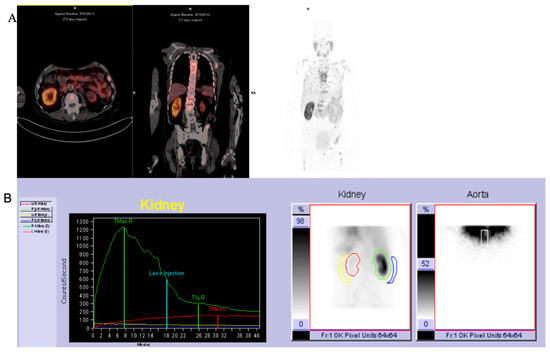

2.1.1. 68Ga-PSMA PET/CT

2.1.2. 68Ga-PSMA PET/CT Image Analysis

2.1.3. 99mTc-MAG3 Renal Scintigraphy